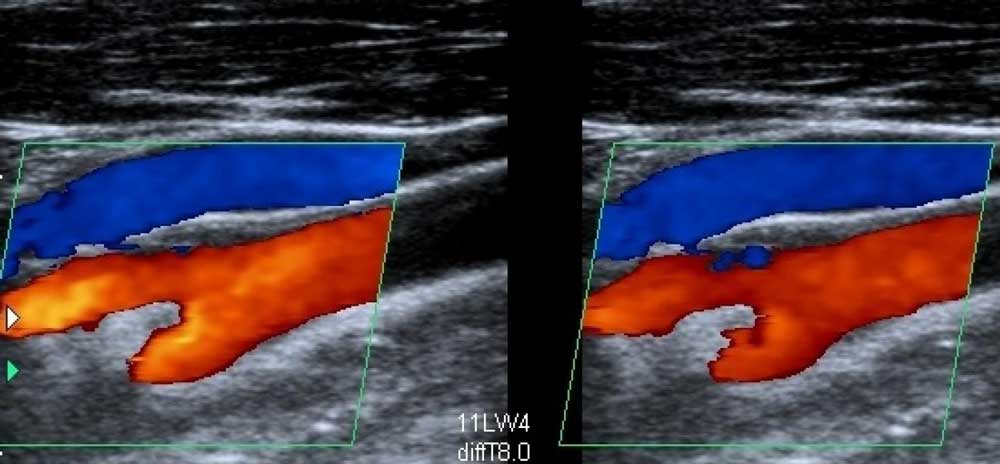

- проведение дуплексного сканирования вен ног, которое позволяет точно определить состояние вен и, в соответствии с ним, подобрать метод лечения;

Наиболее информативный метод диагностики — дуплексное УЗИ. Исследование проводится при наличии симптомов для установления диагноза и для регулярного контроля за состоянием вен. Специалисты рекомендуют проводить его 1-2 раза в год. Безопасная информативная процедура показана в любом возрасте, она безболезненна и может проводиться неограниченное число раз. Ультразвуковое исследование занимает примерно 20-30 минут. На дисплее врач видит изображение, полученное с помощью перемещаемого по коже датчика, и определяет состояние вен и клапанов, наличие или отсутствие тромбов.